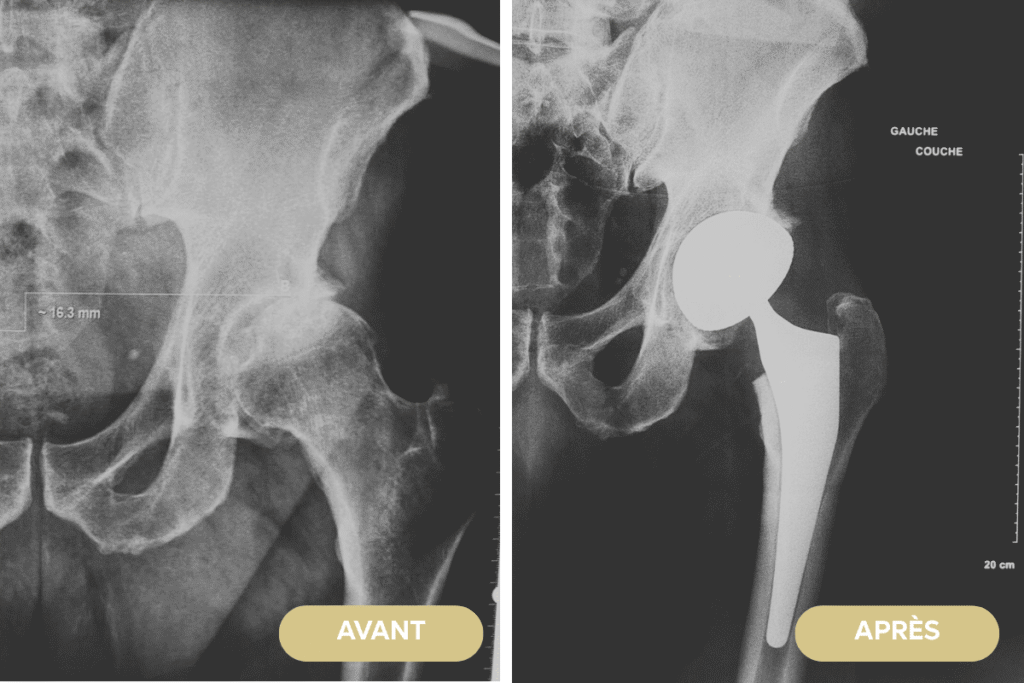

Radiographies pré- et postopératoires d’un patient ayant bénéficié de la mise en place d’une prothèse totale de hanche gauche.

Radiographie, pré et postopératoire, d’un patient ayant bénéficié de la mise en place d’une prothèse totale de hanche gauche. Il présentait une coxarthrose sévère invalidante avec des douleurs importantes inguinales, ainsi que des difficultés à la marche et au chaussage. Je l’ai opéré en chirurgie ambulatoire. L’intervention a consisté en la mise en place d’une tige anatomique non cimentée, associée à un cotyle à double mobilité, par voie postéro-latérale. Le patient est sorti le jour même de l’intervention. Il a été accompagné à son domicile par une prise en charge globale, notamment grâce au médecin traitant et aux infirmières RAAC. Aujourd’hui, à deux ans de l’intervention, il marche sans aucune difficulté et a complètement « oublié » sa prothèse de hanche.